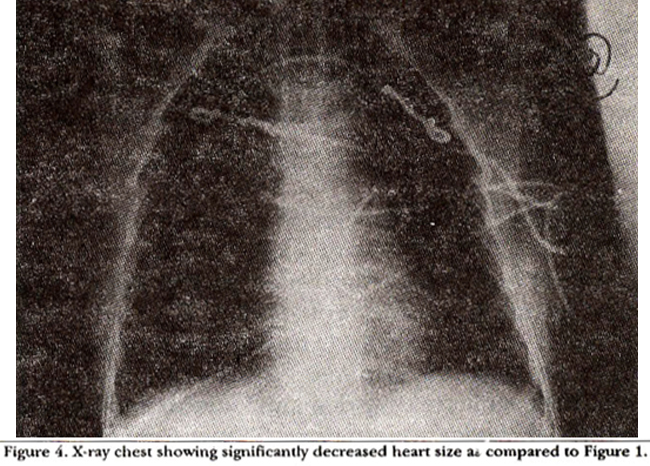

pericardiocentesis Post, x-ray chest showed normal heart size without any pulmonary congestion (Figure 4).